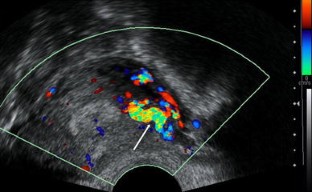

Fig. 2